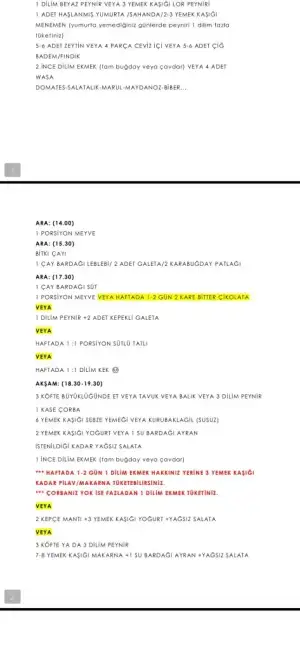

Folik asit içmelisin tabiki gebelikten önce bile içiyorlar. Folat değerin yetersiz değil ama nörolojik bir problem olmasın diye ilk 3 ay gebeler içer. Ama folik asiti doğal yoldan alma fikrini benimseyenler de var. Ben almanı öneritim doktoruna telefonda sorma ihtimalin var mı?Kızlar herkes folic asit içmeye başladı mı?

İlaç içmeme multivitamin vs takviyeye gerek var mı sizce?

Hamilelerde bu değerler kaç olmalı.